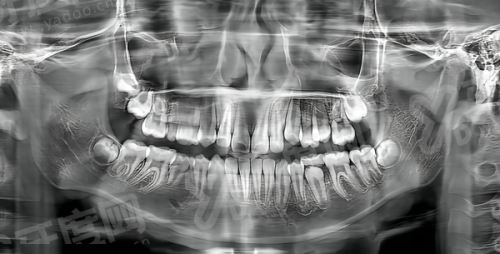

2、给我操作的医生,他有12年的种植经验,术前给我拍了CBCT,拿着影像图一点点跟我讲我的牙槽骨厚度、种植体要放的位置,连我担心的邻牙会不会被影响都讲得明明白白,完全没让我有焦虑感。

1、两家都支持在线预约,我和我爸都是先找在线客服问了基本情况,约了免费的面诊和CBCT拍片,到院直接就能检查,不用像国有医院那样排大半天的队。